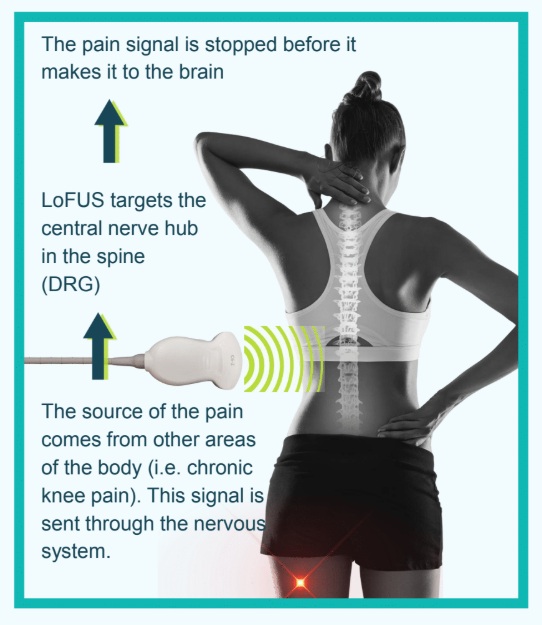

LoFUS is the first medical device to successfully modulate or “turn down” the pain signal at the central nervous system without surgery, injections, or drugs. It is a proprietary solution with an ultrasound applicator that delivers ultrasound waves to a treatment zone personalized for each patient’s anatomy. LoFUS is the only non-surgical way to disrupt spinal pain signals without damaging tissue or nerves.